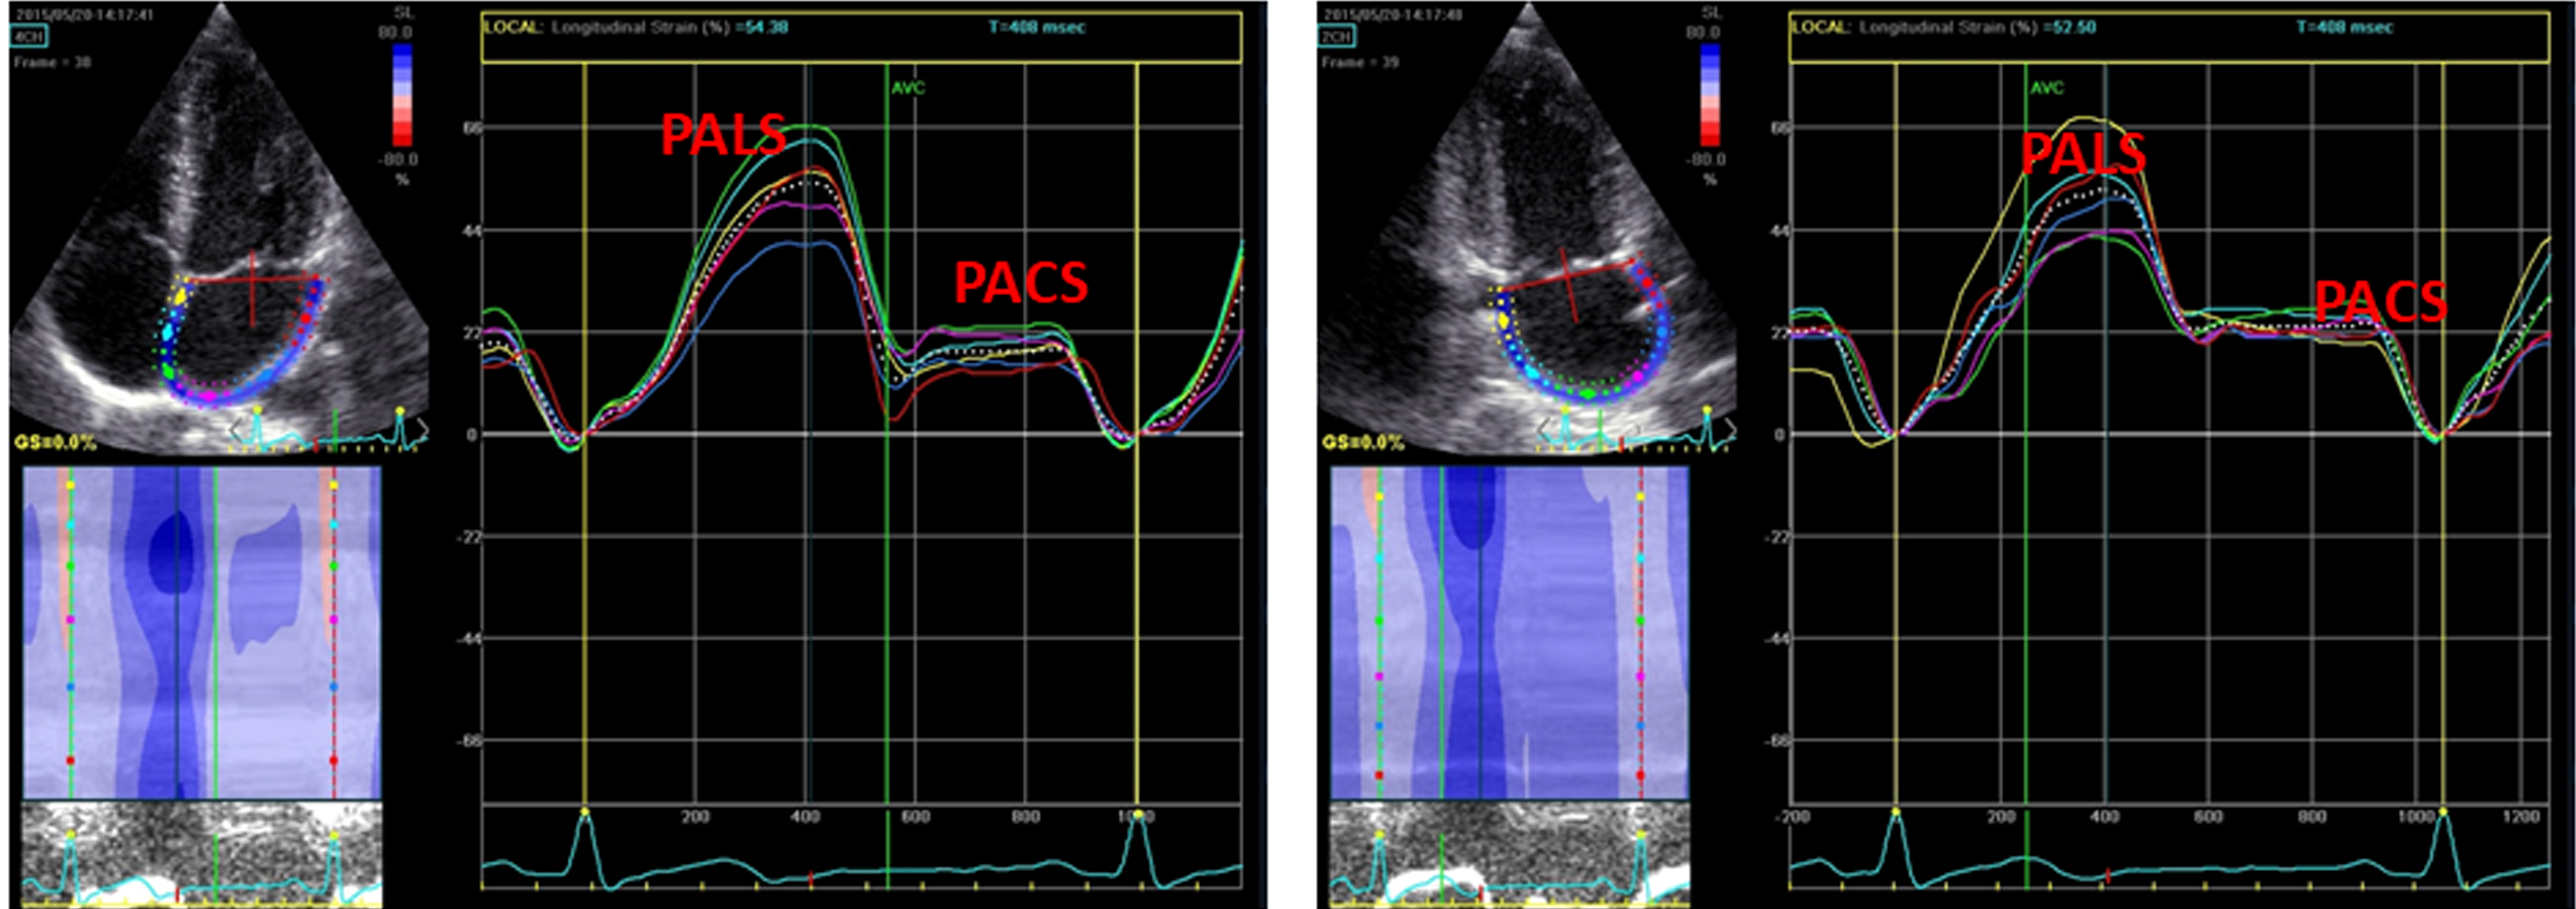

Speckle-tracking echocardiography acquisition and post-processing (EchoPAC, GE, USA) were performed in apical long-axis, 4-chamber, and 2-chamber views of the conventional 2D gray scale images with a stable ECG recording, according to standardized procedures of our laboratory [22, 23]. Global Longitudinal strain (GLS) was calculated by averaging all values of regional peak systolic by a semi-automatic 2D strain software [24]. LA strain was evaluated by 2D speckle tracking recording in the apical 4- and 2- chamber views [25]. LA endocardial border was manually traced, delineating a region of interest (ROI) which consists of 6 segments. After tracking, quality analysis was done by manual adjustment of the ROI, and the longitudinal strain curves generated by the software. LA peak longitudinal deformation (PALS), measured at the end of the reservoir phase, and LA contraction strain (PACS), obtained during LA systole, were determined as the average of regional LA measurements taken in apical 4- and 2-chamber views [2426] (Figure 1).

Figure 1: STE derived methodology to calculate LA strain in apical 4- and 2-chamber views.

Panel A: Apical 4-chamber view, Panel B: Apical 2-chamber view.